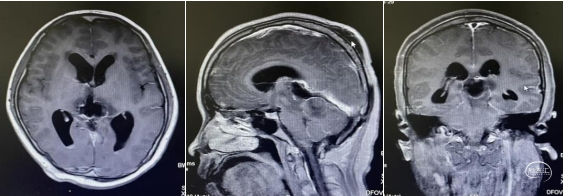

头部磁共振:松果体区可见一稍长-长T1、稍长-长T2信号灶,内可见小片状短丁1信号,增强后实性成分明显不均匀强化,大小约30mmx24mmx33mm,病灶部分伸入第三脑室,第三脑室扩张,双侧丘脑受压移位,中脑导水管,以慕上脑室系统积水扩张,双侧脑室旁可见线样FLAIR高信号。左侧丘脑,左侧脑桥及桥臂可见小片状长T1长T2信号,FLAIR呈高信号。

病理检查:恶性肿瘤,结合免疫组化,诊断为弥漫型儿童高级别胶质瘤(WHO 4级)。免疫组化结果:Olig2(+),GFAP(+),S-100(+),Syn(-),SSTR2A(-),Ki67(约40%+),CD34(-),H3K27M(-),H3K27Me3(+),IDH1(-),P53(突变型),SALL4(-),CK-Pan (-),Desmin(局灶+),HCG(-)INI1(+),SMARCA4(+),BCOR(-)。